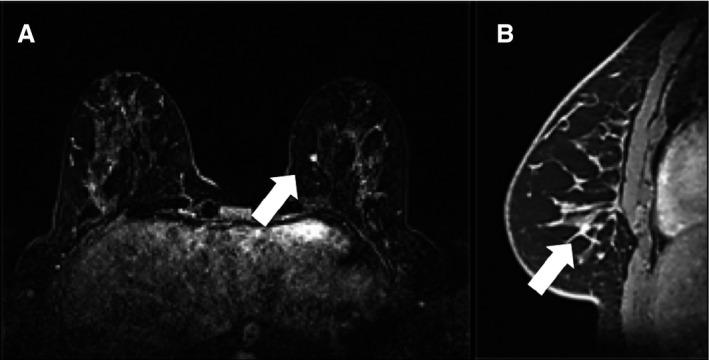

The aim of this study was to evaluate the presence of clinically and mammographically occult disease using breast MRI in a cohort of cancer patients undergoing contralateral prophylactic mastectomy (CPM) and the utmost indication of axillary assessment (sentinel node biopsy (SLNB)) for this side. A retrospective review of patients with unilateral invasive breast cancer or ductal carcinoma in situ (DCIS) from institutional MRI registry data (2004-2010) was conducted. Characteristics of patients undergoing CPM with breast MRI obtained less than 6 month before surgery were evaluated. A total of 2322 consecutive patients diagnosed with DCIS or stage I to III infiltrating breast cancer underwent preoperative breast MRI. Of these, 1376 patients (59.2%) had contralateral clinical breast exam and mammography without abnormalities; and 116 patients (4.9%) underwent CPM (28 excluded patients had breast MRI more than 6 months before CPM). The mean age of the 88 patients was 49 years (range 28-76 years). Two (2.3%) DCIS identified on surgical pathology specimen were not depicted by MRI and the 5 mm T1N0 invasive cancer (1.1%) was identified on MRI. Preoperative MRI showed 95% accuracy to demonstrate absence of occult disease with negative predicted value (NPV) of 98% (95% CI: 91.64-99.64%). Occult disease was present in 3.4% of CPM. MRI accurately identified the case of invasive cancer in this cohort. The high negative predictive value suggests that MRI can be used to select patients without consideration of SLNB for the contralateral side.